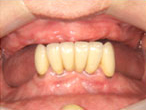

上顎のインプラント治療

上顎は臼歯部の骨量が不足していたためサイナスリフトを行い、約6ヵ月後にインプラント埋入手術を施しました。上下顎のインプラント治療によって患者さんの咬合機能と審美性を大幅に改善することができました。

正面観